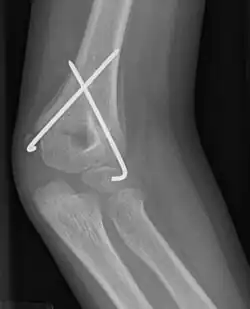

X-ray photograph of a fracture across the humerus, with a pair of wires crossed to pin the fracture

Supracondylar humeral fracture, treated with closed reduction and pinning